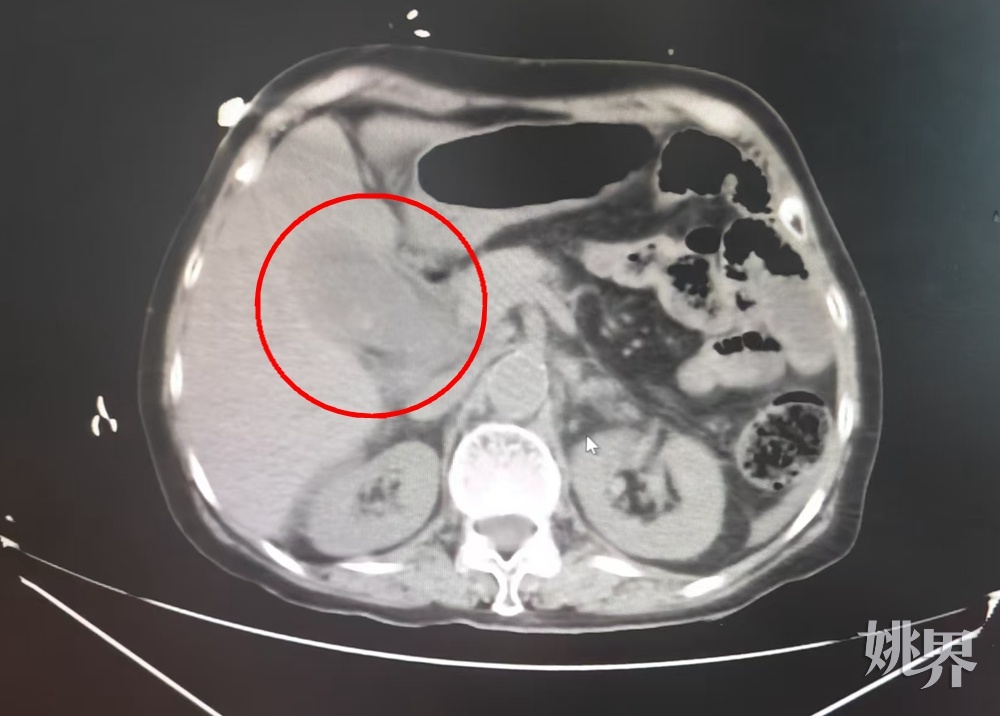

CT显示李奶奶(化姓)胆囊内被密密麻麻的结石塞满

手术当天,77岁的李奶奶(化姓)因腹痛、恶心、呕吐、发热等症状,被家人紧急送往余姚市中医医院急诊救治。经过初步检查,李奶奶被诊断为胆囊结石伴急性胆囊炎。剧烈疼痛让李奶奶脸色苍白、大汗淋漓,甚至一度出现了休克症状。